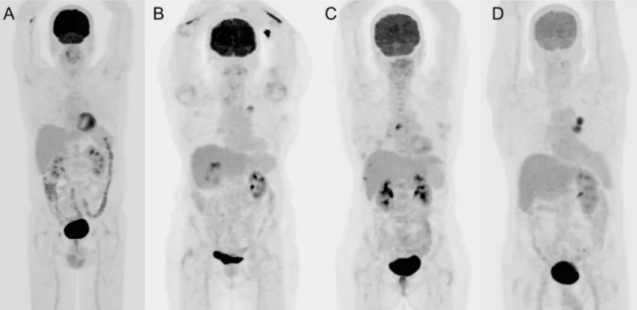

What are the 4 types of PET acquisitions?

Limited area

Dynamic

Skull-base to mid-thigh

Whole body

When would we use a dynamic acquisition?

Isn’t common – often seen in research to find the ideal radiotracer for a case

What is the skull-base to mid-thigh acquisition?

Most common acquisition for PET imaging

We would start scanning the patient from their eyes → end at their thighs

When would we perform a whole body acquisition?

If the patient has melanoma – want to image cancer from head-to-toe